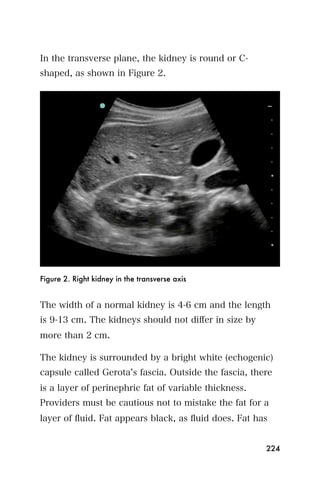

diaphragm is marked with an arrow.

It is important to also look for blood in the pelvis, and

left upper quadrant as is performed in the trauma exam

described in the Trauma chapter. If ruptured ectopic

pregnancy is suspected, and bleeding is found within the

108

abdomen, this finding is an indication for immediate

surgery to control the bleeding.

Findings: Contents within uterus

Early in the pregnancy, a normal baby lives in a sack of